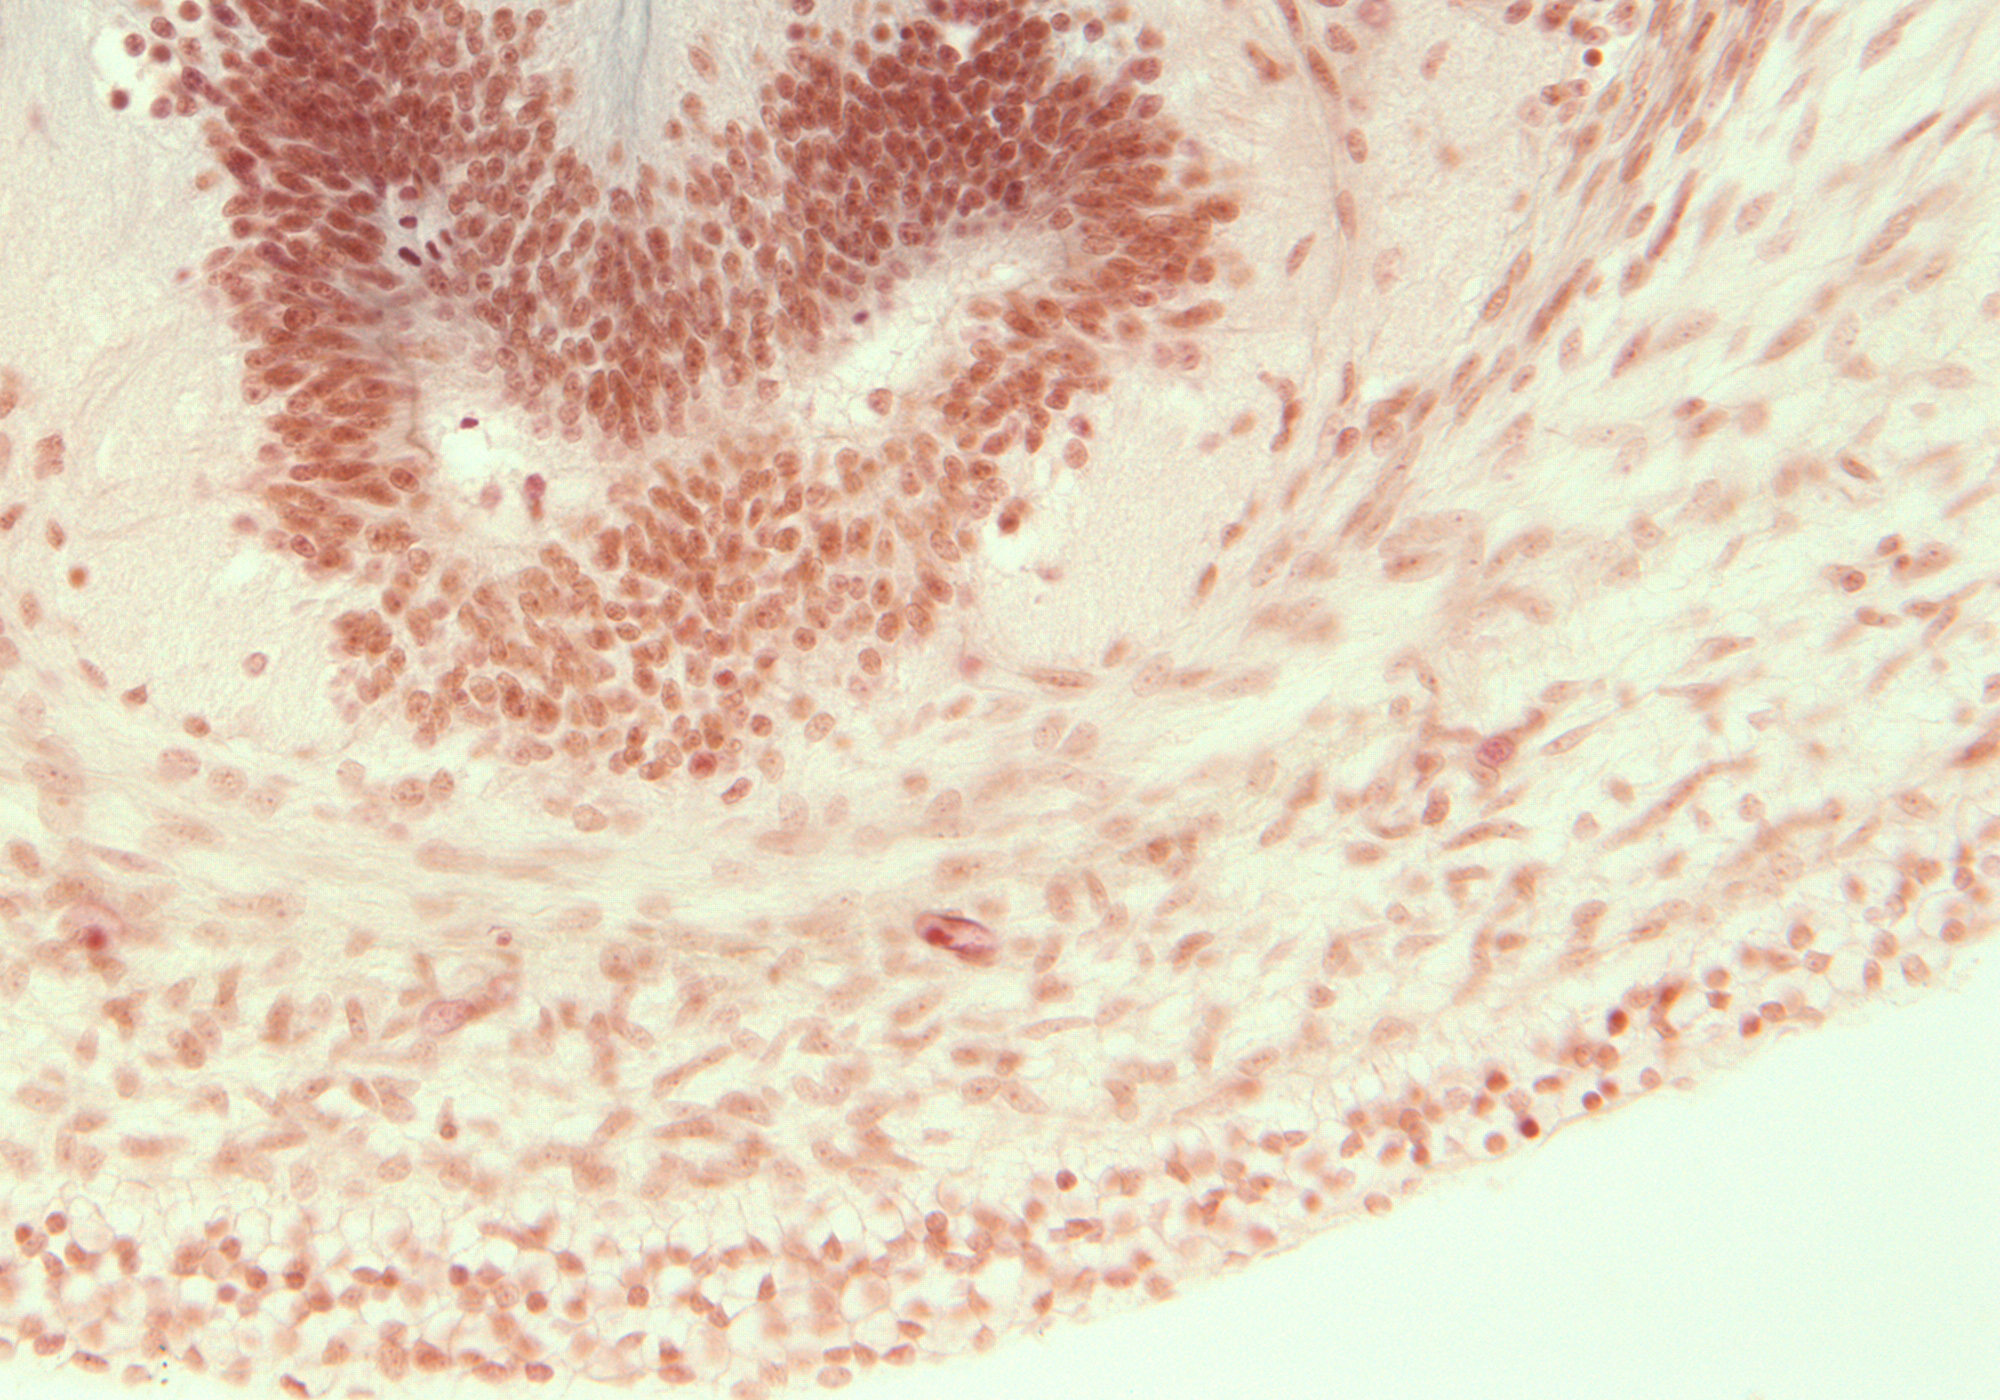

Tissue

–

Caudal End of Spinal Cord

Carnegie Embryo #9226

Location:

207-01-01